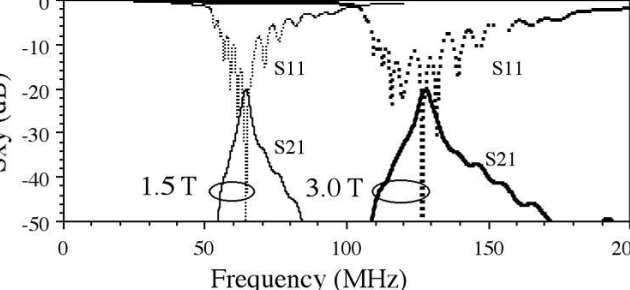

Richard Syms, Evi Kardoulaki and Ian Young

Simon Taylor-Robinson, Chris Wadsworth and Marc Rea (St Mary’s Hospital)

We have developed a magnetic resonance imaging duodenoscope, by combining non-magnetic endoscope components with a thin-film receiver based on a magneto-inductive waveguide. The waveguide elements consist of figure-of-eight shaped inductors formed on either side of a flexible substrate and parallel plate capacitors that use the substrate as a dielectric. Operation has been simulated using equivalent circuit models and by computation of sensitivity patterns. Circuits have been fabricated for operation at 127.7 MHz by double-sided patterning of copper-clad Kapton and assembled onto non-magnetic flexible endoscope insertion tubes. Operation has been verified by bench testing and by 1H MRI at 3T using phantoms. The receiver can form a segmented coaxial image along the length of the endoscope, even when bent, and shows a signal-to-noise-ratio advantage over a surface array coil up to three times the tube diameter at the tip. Initial immersion imaging experiments have been carried out and confirm an encouraging lack of sensitivity to RF heating.

|---|

| Mechanical arrangement of metameterial endoscope. |

|---|

| Electrical layout of thin film PCB (a), and equivalent circuit models for imaging (b) and electrical testing (c). |

|---|

| Arrangement for magnetic resonance imaging with cuboid phantoms (a), body coil image showing effective decoupling (b) and metamaterial coil image, showing segmented field of view (c). |